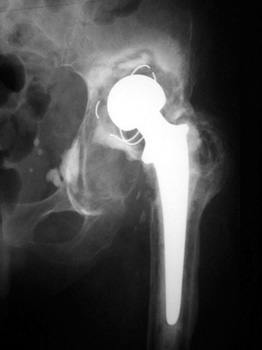

OSTEOLYSIS—Gruen zones 2 and 3, with markedly thinned femoral cortex, placing patient at risk for pathologic fracture